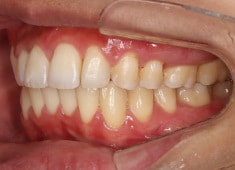

治療開始時